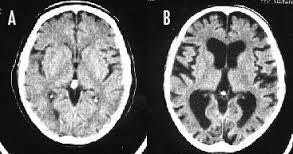

きっと画像のBみたいな脳ミソしてるんだね

発達障害の物分かりの悪さに加えて

喫煙の影響で脳が萎縮してるんじゃ

認知機能に異常をきたしてるのも当たり前

>>92の奴のおかげでたばこを吸ってなくてもBの脳になってしまうことが立証されたぞw